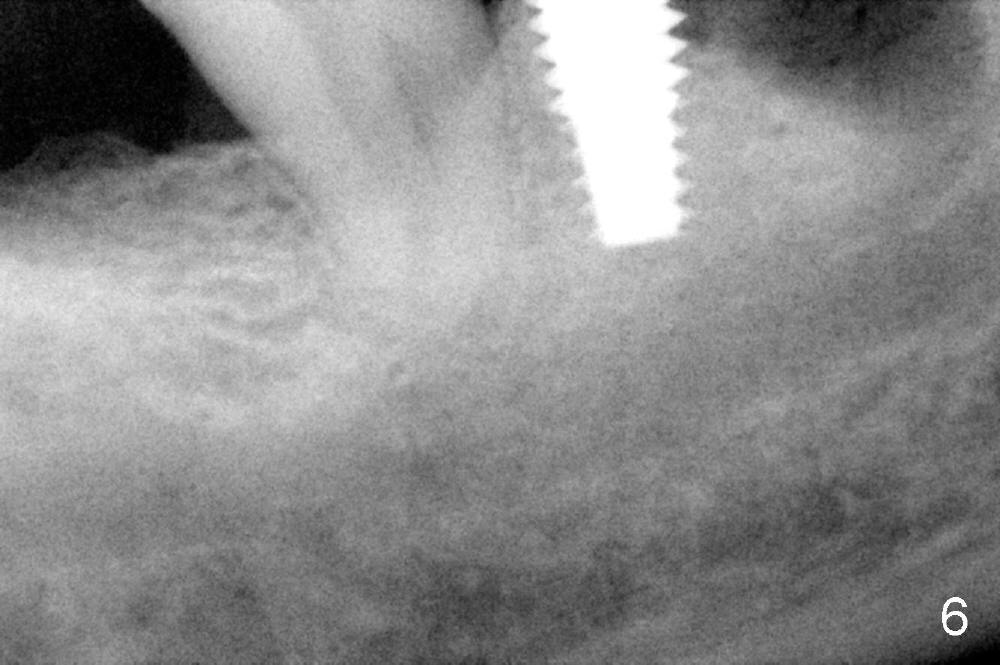

As to where to place an implant, we try to engage the largest tap (8 mm in diameter) into the mesial socket without binding. The buccal plate of the mesial socket is missing.  It is risky to extend osteotomy in the mesial socket.  Besides, the septum (Fig. 4 S) is not as tall as the distal socket (D).  It appears that the distal socket is the safest place to place an implant.  Furthermore, no drill is used for distal osteotomy.  Instead two osteotomes (3.5x15 and 4x15 mm tapered osteotomes) are used to expand the distal socket with intention to push the septum mesially.  Since the bone density is high, the osteotomes seem not to work as effectively as expected.  Then a 4.5x17 mm tap is placed at the depth ~ 14 mm with stability (Fig.5).  Finally a 5x14 mm tissue-level implant is placed with insertion torque >60 Ncm (Fig.6).  Allograft is placed in the mesial socket and buccal aspect of the distal socket, followed by insertion of collagen plug and membrane (Fig.7).  After insertion of an abutment (Fig.8 (taken 6 days postop) *), perio dressing (P) is applied to cover the wound.  There is no postop paresthesia.